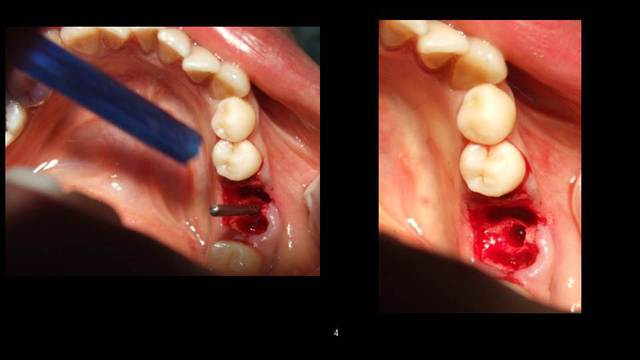

Cookie Consent byPrivacyPolicies.comInsertion immediate au niveau de 46 dans le septum - Eugenol

Insertion immediate au niveau de 46 dans le septum